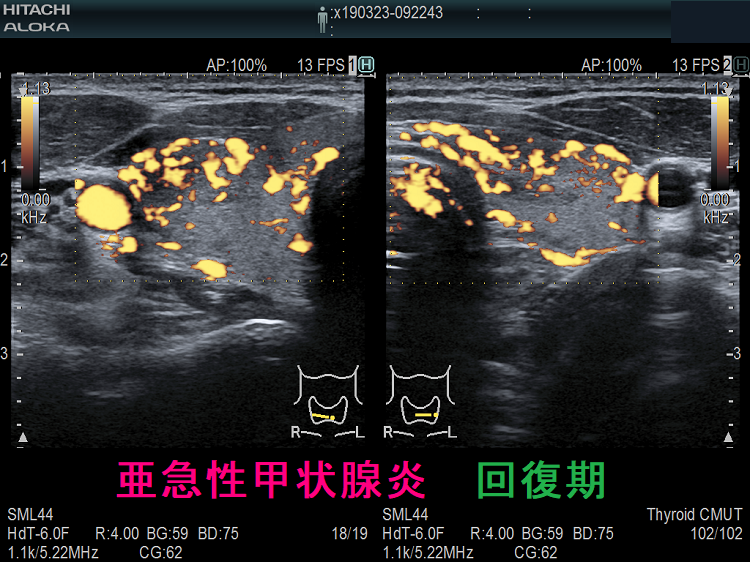

長崎甲状腺クリニック(大阪)オリジナルの亜急性甲状腺炎の治療は、中途再燃・再発を防ぐため、超音波(エコー)検査で炎症範囲を毎回調べ、改善度に応じてステロイド量を調整。炎症の強い部分は黒く、血流乏しく、エラストグラフィーで青くなる。副作用チェックはステロイド肝障害・膵炎・筋障害・低カリウム血症・糖尿病。甲状腺乳頭癌の合併、亜急性甲状腺炎ではなく、甲状腺乳頭癌の事も。亜急性甲状腺炎はバセドウ病,橋本病に合併、あるいは誘発する事も。頚部腫大、甲状腺中毒症が先行する場合、エコー検査で偶然見つかる事も。数年かかっても完全治癒しない亜急性甲状腺炎も稀に存在。

下は亜急性甲状腺炎の超音波(エコー)画像で、炎症の強い部分は黒く、エラストグラフィーでは青くなります。